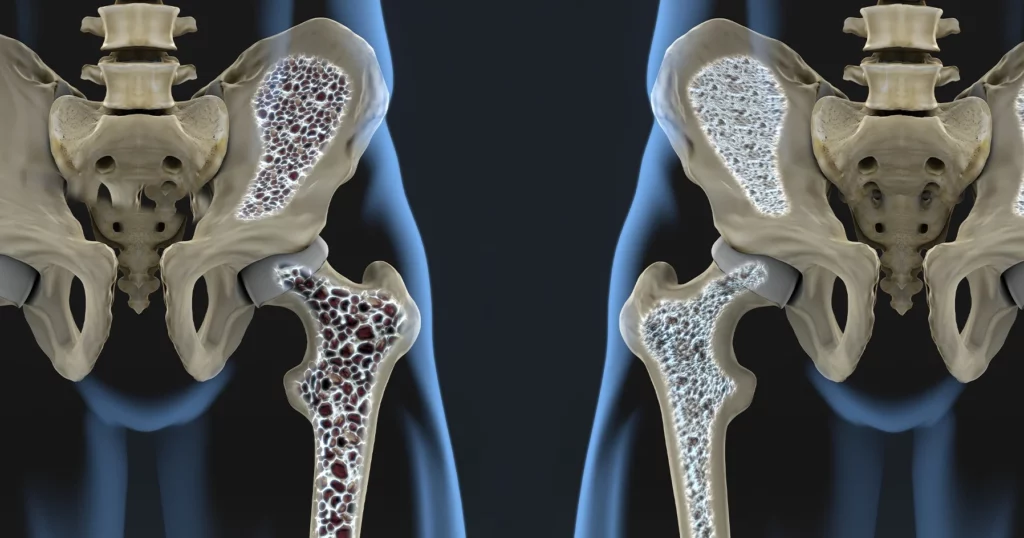

O descoperire majoră în domeniul medical ar putea revoluționa tratamentul osteoporozei, boala care afectează milioane de oameni la nivel mondial. O echipă de cercetători din Germania a identificat un receptor din organism, numit GPR133, care pare să joace un rol crucial în controlul rezistenței oaselor. Activarea acestui receptor a demonstrat, în cadrul experimentelor pe animale, efecte pozitive semnificative asupra densității osoase și refacerii țesutului afectat.

Osteoporoza, caracterizată prin subțierea și fragilizarea oaselor, este o problemă de sănătate publică majoră, mai ales în rândul persoanelor în vârstă. Tratarea acestei afecțiuni este adesea dificilă și limitată la medicamente care încetinesc pierderea osoasă, cu efecte secundare potențiale. Descoperirea receptorului GPR133 oferă o nouă perspectivă, deschizând calea spre terapii mai eficiente și cu mai puține riscuri.

Cercetările au arătat că stimularea receptorului GPR133 duce la creșterea densității osoase și la regenerarea țesutului osos deteriorat. Aceste rezultate, obținute în experimente pe animale, sunt extrem de promițătoare și sugerează că activarea acestui receptor ar putea fi o strategie eficientă în tratamentul osteoporozei. În prezent, se lucrează la dezvoltarea unor medicamente care să țintească specific acest receptor.

Studiile au arătat că activarea receptorului GPR133 poate duce la o îmbunătățire semnificativă a structurii osoase și la reducerea riscului de fracturi. Acest lucru ar putea schimba fundamental modul în care este abordată osteoporoza, oferind pacienților o modalitate de a-și recapăta forța și densitatea osoasă pierdută.